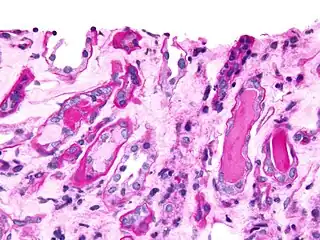

| Top: The most common site of bone lesions is the spine Bottom: Micrograph of a plasmacytoma, H&E stain | |

Bone marrow aspirate showing the histologic correlate of multiple myeloma under the microscope, H&E stain -

Plasmacytoma, H&E stain -

Histopathology

A bone marrow biopsy is usually performed to estimate the percentage of bone marrow occupied by plasma cells. This percentage is used in the diagnostic criteria for myeloma. Immunohistochemistry (staining particular cell types using antibodies against surface proteins) can detect plasma cells that express immunoglobulin in the cytoplasm and occasionally on the cell surface; myeloma cells are often CD56, CD38, CD138, and CD319 positive and CD19, CD20, and CD45 negative.[15] Flow cytometry is often used to establish the clonal nature of the plasma cells, which will generally express only kappa or lambda light chain. Cytogenetics may also be performed in myeloma for prognostic purposes, including a myeloma-specific fluorescent in situ hybridization and virtual karyotype.

The plasma cells seen in multiple myeloma have several possible morphologies. First, they could have the appearance of a normal plasma cell, a large cell two or three times the size of a peripheral lymphocyte. Because they are actively producing antibodies, the Golgi apparatus typically produces a light-colored area adjacent to the nucleus, called a perinuclear halo. The single nucleus (with inside a single nucleolus with vesicular nuclear chromatin) is eccentric, displaced by an abundant cytoplasm. Other common morphologies seen, but which are not usual in normal plasma cells, include:

- Bizarre cells, which are multinucleated

- Mott cells, containing multiple clustered cytoplasmic droplets or other inclusions (sometimes confused with auer rods, commonly seen in myeloid blasts)

- Flame cells, having a fiery red cytoplasm[43][44]